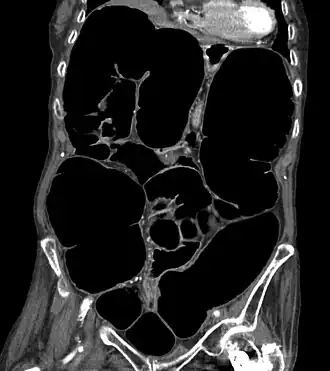

Description de l'image Ogilvie ct coronal.jpg.

Le syndrome d’Ogilvie est une dilatation aigüe du côlon sans cause organique ni obstacle, ni tumeur, ni lésion inflammatoire, ulcéreuse ou ischémique[2]. Il s’agit d’un syndrome qui doit être reconnu et traité précocement en raison du risque évolutif de perforation de cæcum (mortalité 40 %)[3].

Le scanner abdomino-pelvien avec injection de produit de contraste iodé est l'examen de référence[4] : il montrera des signes pathognomoniques d'occlusion intestinale (niveaux hydro-aériques, dilatation des anses intestinales) sans zone de transition et en l'absence d'obstacle obstruant la lumière intestinale.